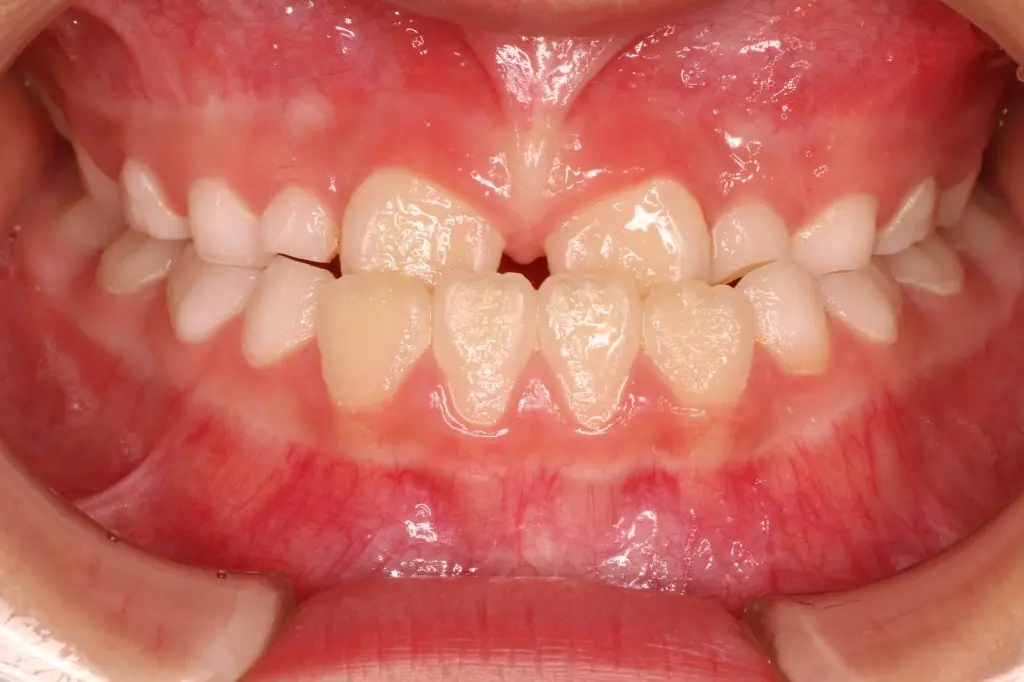

【治療開始時】

6才、下の前歯が上の前歯より前に出ている「反対咬合」の状態。顎の成長バランスが悪くなる恐れがありました。